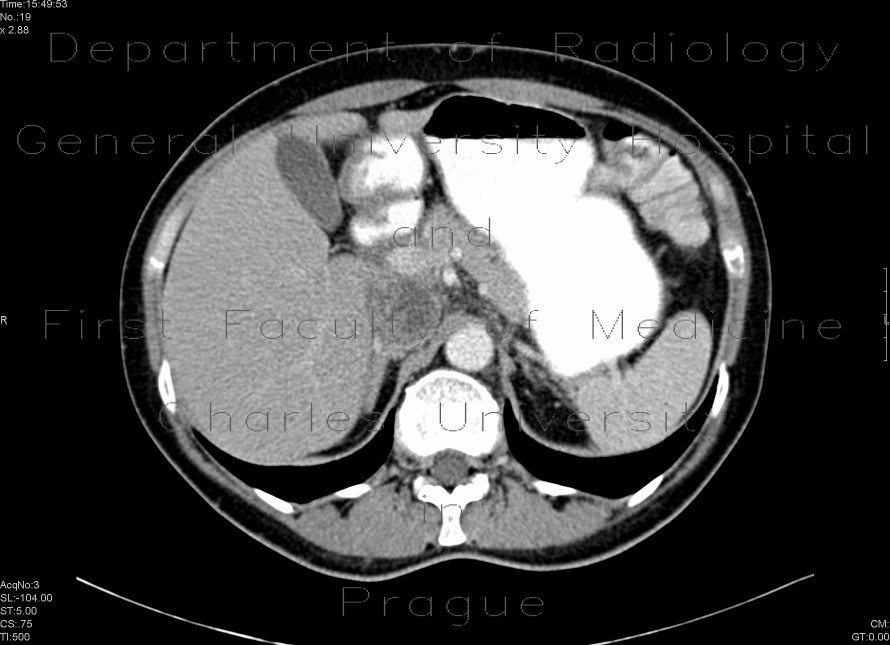

Non-homogeneous, slightly enhancing tumorous mass filling and distending the lumen of the inferior vena cava.

Radiology image - Tumorous mass in vena cava inferior: Abdomen, Vessels: CT - Computed tomography